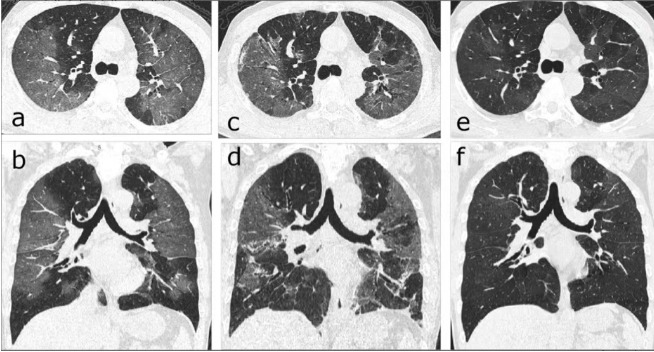

【医声守护·科普】第325期:为什么医生总让肺结节患者做薄层CT这项检查?